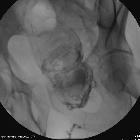

CT

CT is the most common modality used for assessment of enterocutaneous fistulas, especially with the use of fistulography. The injection of positive contrast well-delineates the fistulous tract and its branching pattern and connections. CT also enables multiplanar reconstruction and thin cuts for good anatomical details. CT is also helpful for assessment of adjacent soft tissues, identifying associated abscesses and features of possible non-surgical etiologies like inflammatory bowel diseases.